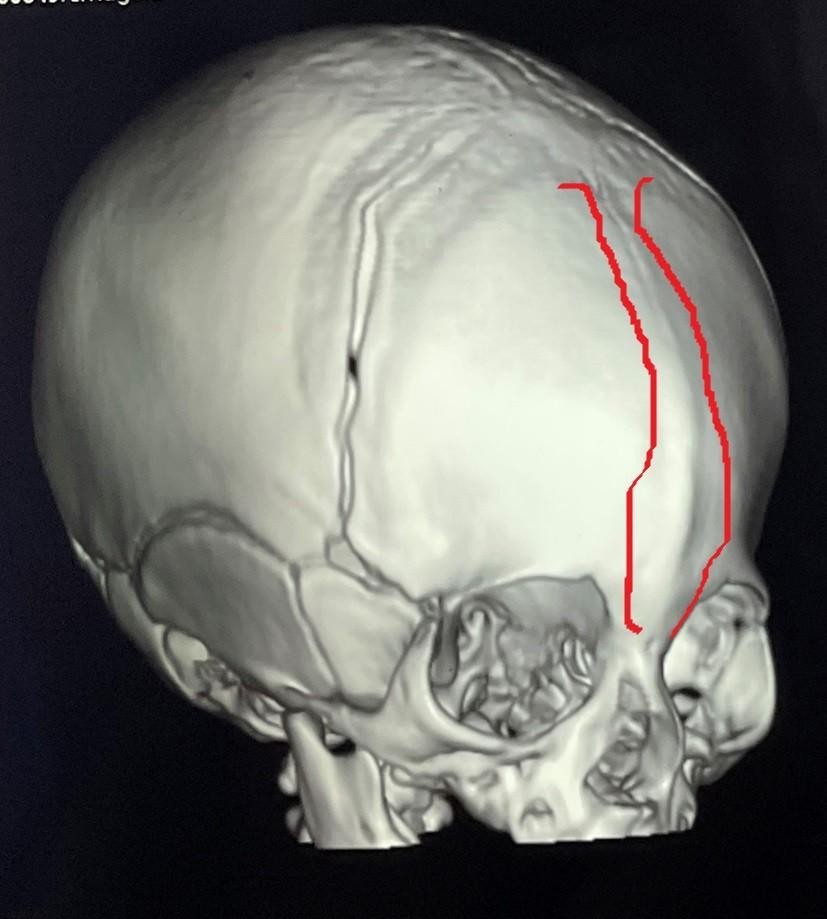

Trigonocephaly Correction Surgery in a Two-Month-Old Infant

A successful cranial correction surgery was performed on a two-month-old infant suffering from trigonocephaly, a condition characterized by a triangular-shaped head. This type of cranial deformity results in a triangular head appearance with a prominent forehead ridge. The goal of the surgery was to correct the skull shape to ensure normal brain development and protect the child from future complications.

• Reshaping cranial bones to correct triangular form

• Removing prominent forehead bony ridge

• Precise pre-operative planning using 3D imaging